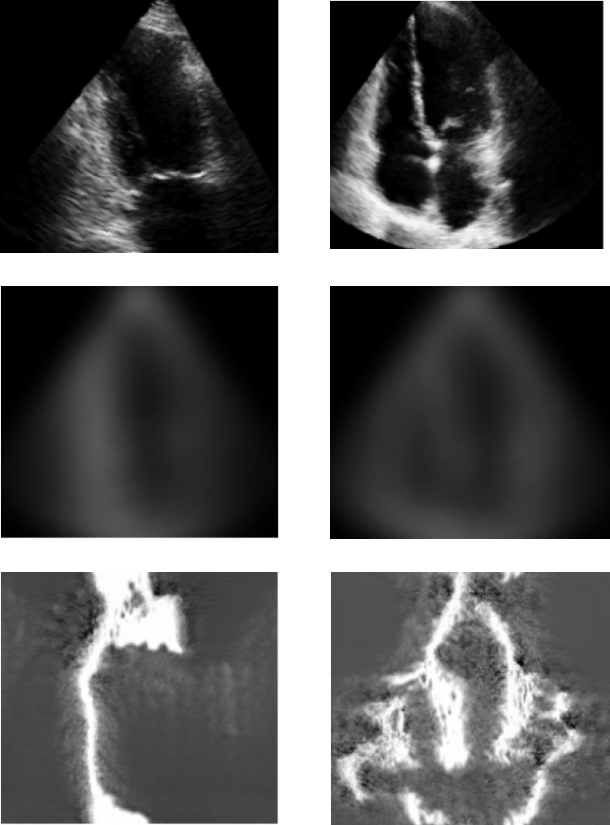

We note that requiring a mean image from a dataset allows us to impart class-specific impressions without violating privacy regulations such as re-identification and differential privacy [1]. It is also important to note that the averaged images, as shown in the second row of Fig. 2, are visually different from the real images shown in the first row of Fig. 2. This is in line with the aim of our data synthesis, which is to generate images following the distributions of past classes rather than reconstructing training data points, as model inversion attacks do [30, 34, 101].

Fig. 4: Datasets’ samples. Each dataset’s first row shows samples from two different classes, the second row is the mean initialization of the respective class, and the third row is the synthesized images. Best view in coloured.